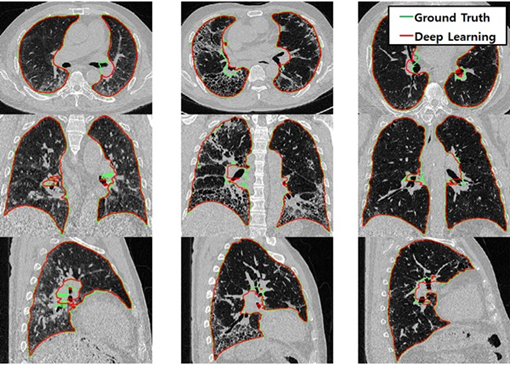

이런 기술들은 자율주행 자동차, 의료 영상 분석(CT, MRI 진단), 보안 카메라 감시 시스템 등 우리 생활 곳곳에서 사용되고 있습니다.